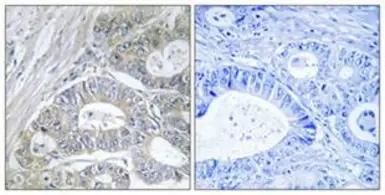

GPRIN2 antibody

Cat. No. GTX87076

ApplicationsIHC-P

ReactivityHuman